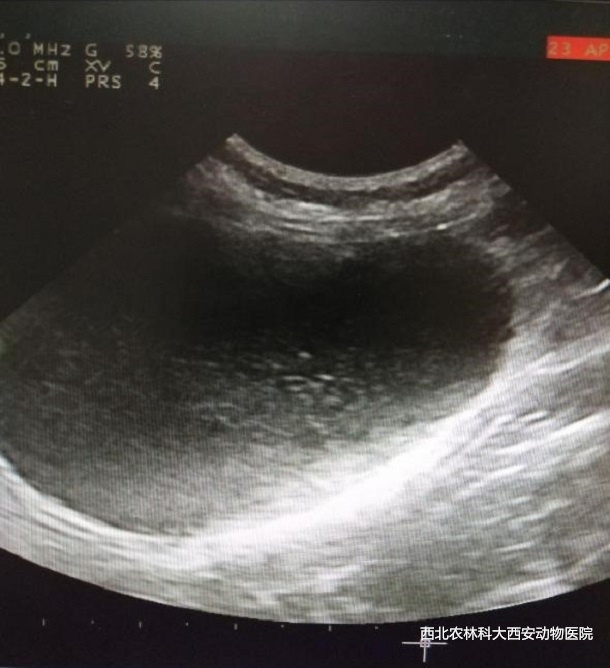

輔助檢查:血常規(guī)、生化、血氣和尿沉渣檢查異常指標見(表1),超聲檢查:可見膀胱內散在高回聲影像,膀胱粘膜欠光滑見(圖1)。

圖一